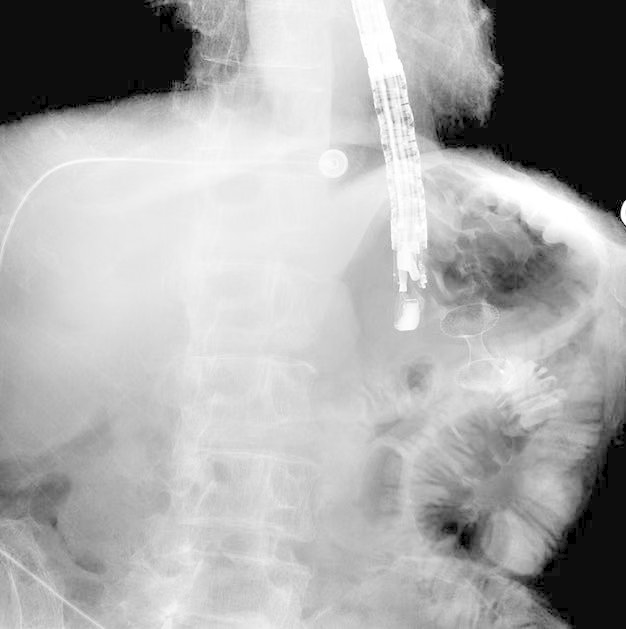

术中影像

整个手术过程一气呵成,用时不到一小时。术后,患者返回病房,未出现并发症。